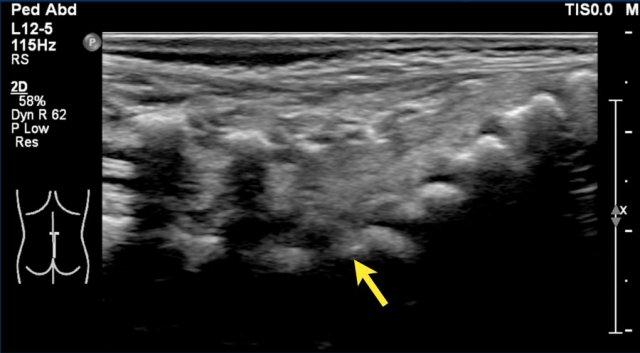

Vị trí của nón tủy

Cách tốt nhất để xác định vị trí của nón tủy là nhận diện khớp thắt lưng-cùng tại góc ưỡn giữa các đốt sống thắt lưng và cùng (mũi tên).

Có thể hữu ích khi gấp và duỗi khung chậu để quan sát điểm chuyển động của xương cùng.

Ở trẻ sơ sinh này, khớp thắt lưng-cùng khó nhận diện hơn do không có góc nhọn rõ ràng.

Các số thứ tự chúng tôi đã đánh dấu có thể không chính xác.

Nếu còn nghi ngờ, hãy chụp ảnh toàn cảnh hoặc ảnh kép của cột sống thắt lưng-cùng và so sánh số đốt sống đếm từ dưới lên với phim X-quang thẳng nghiêng.